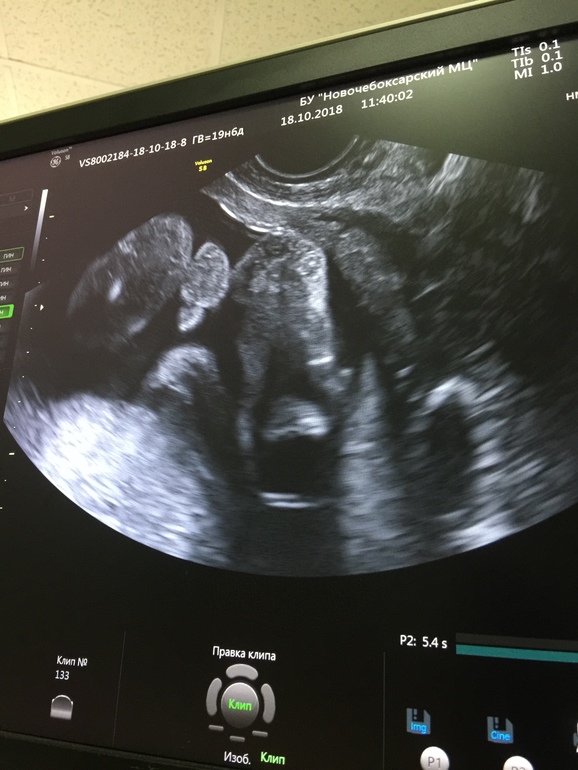

П.с. 18 октября на узи в 20 недель я узнала точно, что у меня будет мальчик) ни одной слезинки, я очень рада сейчас и жду скорее встречи. Хорошо, что я тогда порыдала, и осознала, и свыклась к 20 неделе.